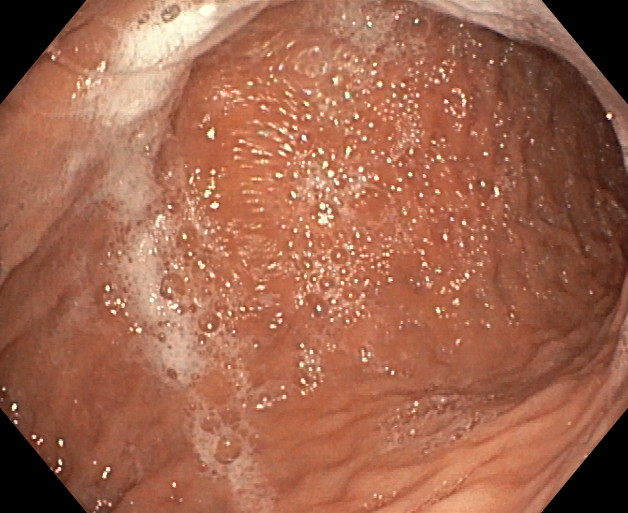

BALÓN INTRAGÁSTRICO

El balón intragástrico es un implante temporal de silicona, que rellenamos con suero, normalmente unos 500-600 cc, con un colorante (azul de metileno) para detectar cualquier posible anomalía futura (pérdida de contenido o rotura), una vez se aloja en el estómago y ocupa una parte importante del mismo. Esto genera dos mecanismos clave para aumentar la saciedad y por ello, perder peso:

- Ocupación de espacio: El dispositivo se aloja libremente en el estómago y genera ya de por sí una sensación de saciedad, ya que tiene entre 10 y 12 cm de diámetro.

- Enlentece la digestión de la comida: El balón dificulta el paso de la comida hacia el intestino, haciendo el proceso más largo en el tiempo. En condiciones normales, la comida tarda una hora aproximadamente en digerirse y pasar al intestino en donde se absorbe. En este caso, la comida permanece más tiempo en el estómago y hace que la saciedad se mantenga más tiempo, ayudando a no pasar hambre, sobre todo en el momento más crítico del día, que suelen ser las horas vespertinas.

Está indicado, como primera opción terapéutica, para pacientes con obesidad leve-moderada (IMC entre 30 y 35) o pacientes con IMC entre 35 y 40 que rechazan otros procedimientos.

Su colocación se realiza en la mayoría de las ocasiones por gastroscopia con sedación profunda administrada y controlada por anestesista, siendo una técnica ambulatoria (no precisa ingreso hospitalario) y su retirada, tras haber cumplido su función a los 6-12 meses, dependiendo de cada caso concreto, por gastroscopia con intubación y anestesista general, para minimizar los posibles inconveniente inherentes a la técnica, igualmente de forma ambulatoria.

La pérdida de peso suele situarse entre los 20-25 kg de media, llegando algunos pacientes a perder más de 35-40 kg, dependiendo del tipo de balón empleado (de 6 o 12 meses), pero puede tener el inconveniente de una re-ganancia tras su retirada si antes no se han implementado unos buenos hábitos higiénicos y dietéticos, siendo aconsejable desde su inicio el asesoramiento por endocrino, nutricionista y/o psicólogo.